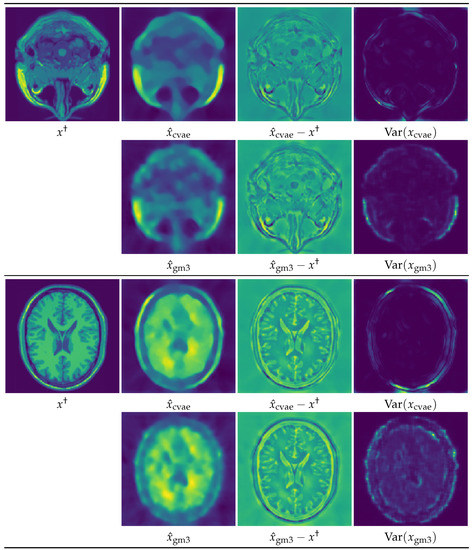

5. Numerical Experiments and Discussions